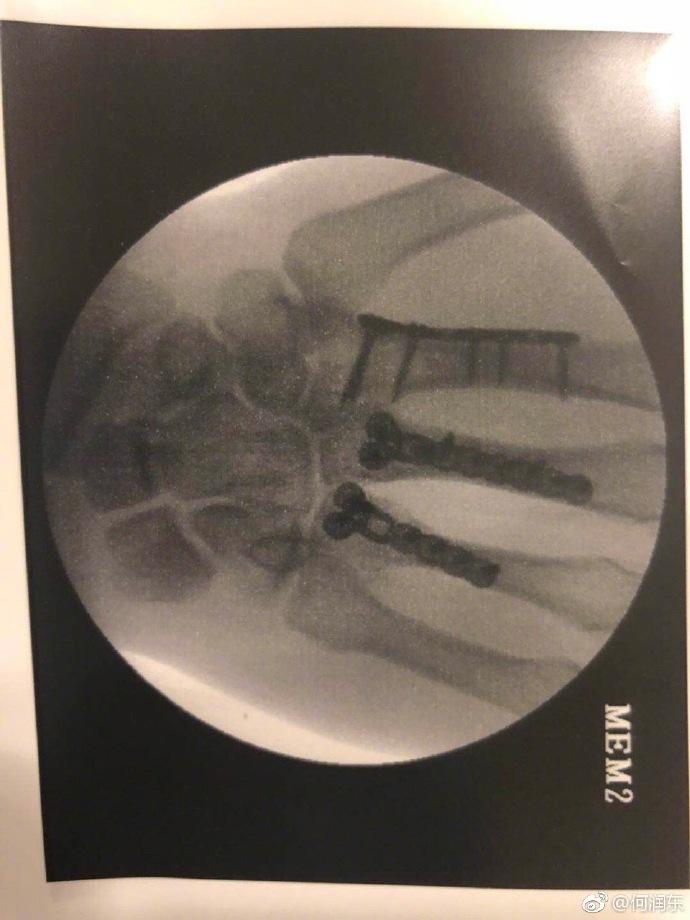

他受伤的伤情才不止这一点,另一张X光片明显看得出来有三根手指都做了固定处理。黑乎乎的阴影,看着也是让人毛骨悚然。

这般惨痛,没想到何润东心情似乎还是不错的,三根钢爪子已经有了,“当我能摆脱残障式健身的那一刻,我将升级为金刚狼。”